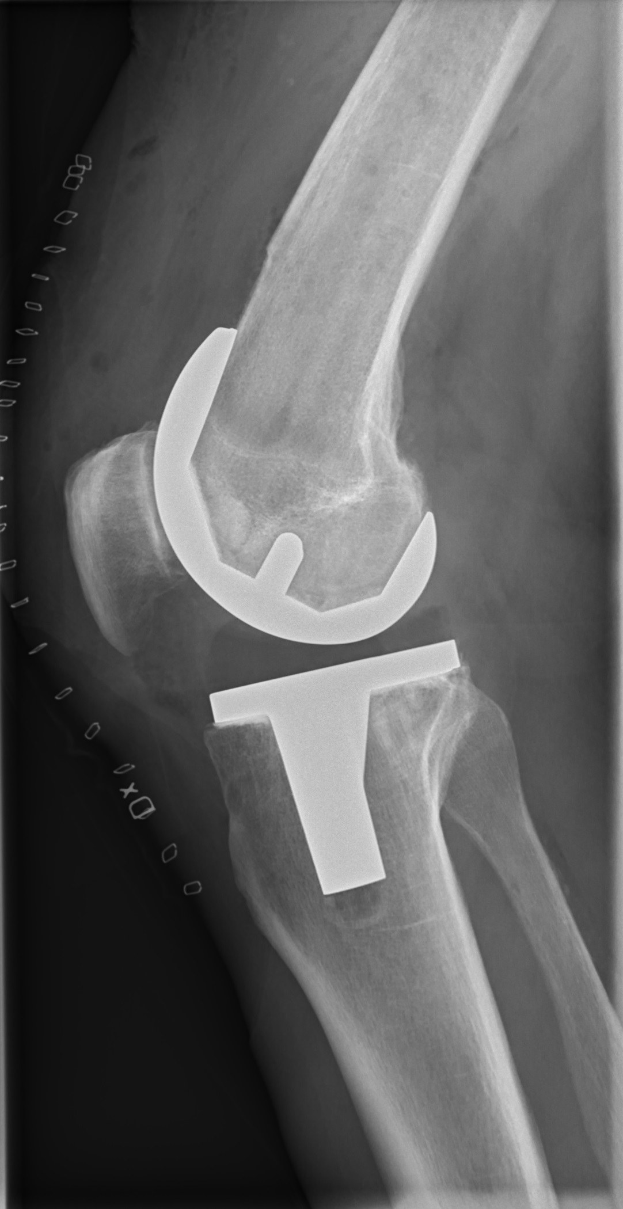

Verletzungspech kommt hinzu: Hack, einer der wenigen Lichtblicke im Pokal, musste sich wegen eines Meniskusrisses im rechten Knie operieren lassen. Sein Ausfall wird mehrere Wochen dauern und hinterlässt eine Lücke im Angriff.